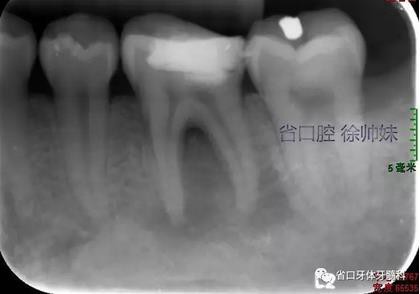

現(xiàn)病史:6個月前左下后牙區(qū)牙齦腫脹,反復(fù)溢膿,無明顯其他不適。4月前于我院牙體牙髓科(圖1)就診,診斷為“36牙周牙髓聯(lián)合病變”,建議試行36根管治療+牙周治療保留患牙,患者當(dāng)時未行治療?,F(xiàn)再次來我院牙體牙髓科要求進一步診治。

圖1 術(shù)前4月的根尖片